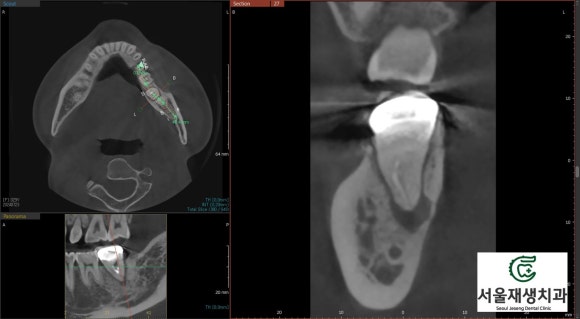

CT를 촬영하여

턱뼈나 신경과의 관계를 파악합니다.

다행히 해당 치아의 염증이

신경관과는 거리가 있으나,

크기가 상당히 커져서

남아있는 뼈의 두께가

아슬아슬하게 보입니다.

조속한 치료가 필요한 상태입니다.

CT를 촬영해서 경과를 관찰해봅니다.

뿌리 끝 염증의 사이즈가 1/4 정도로

크게 감소한 것을 볼 수 있습니다.

이정도면 충분합니다.

나머지 빈공간은

수개월~수년에 걸쳐 내 몸이

천천히 채워나갈겁니다^^